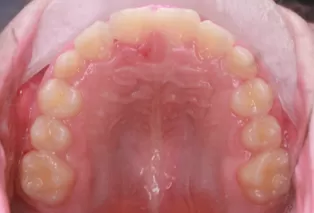

Photos intra-orales après traitement